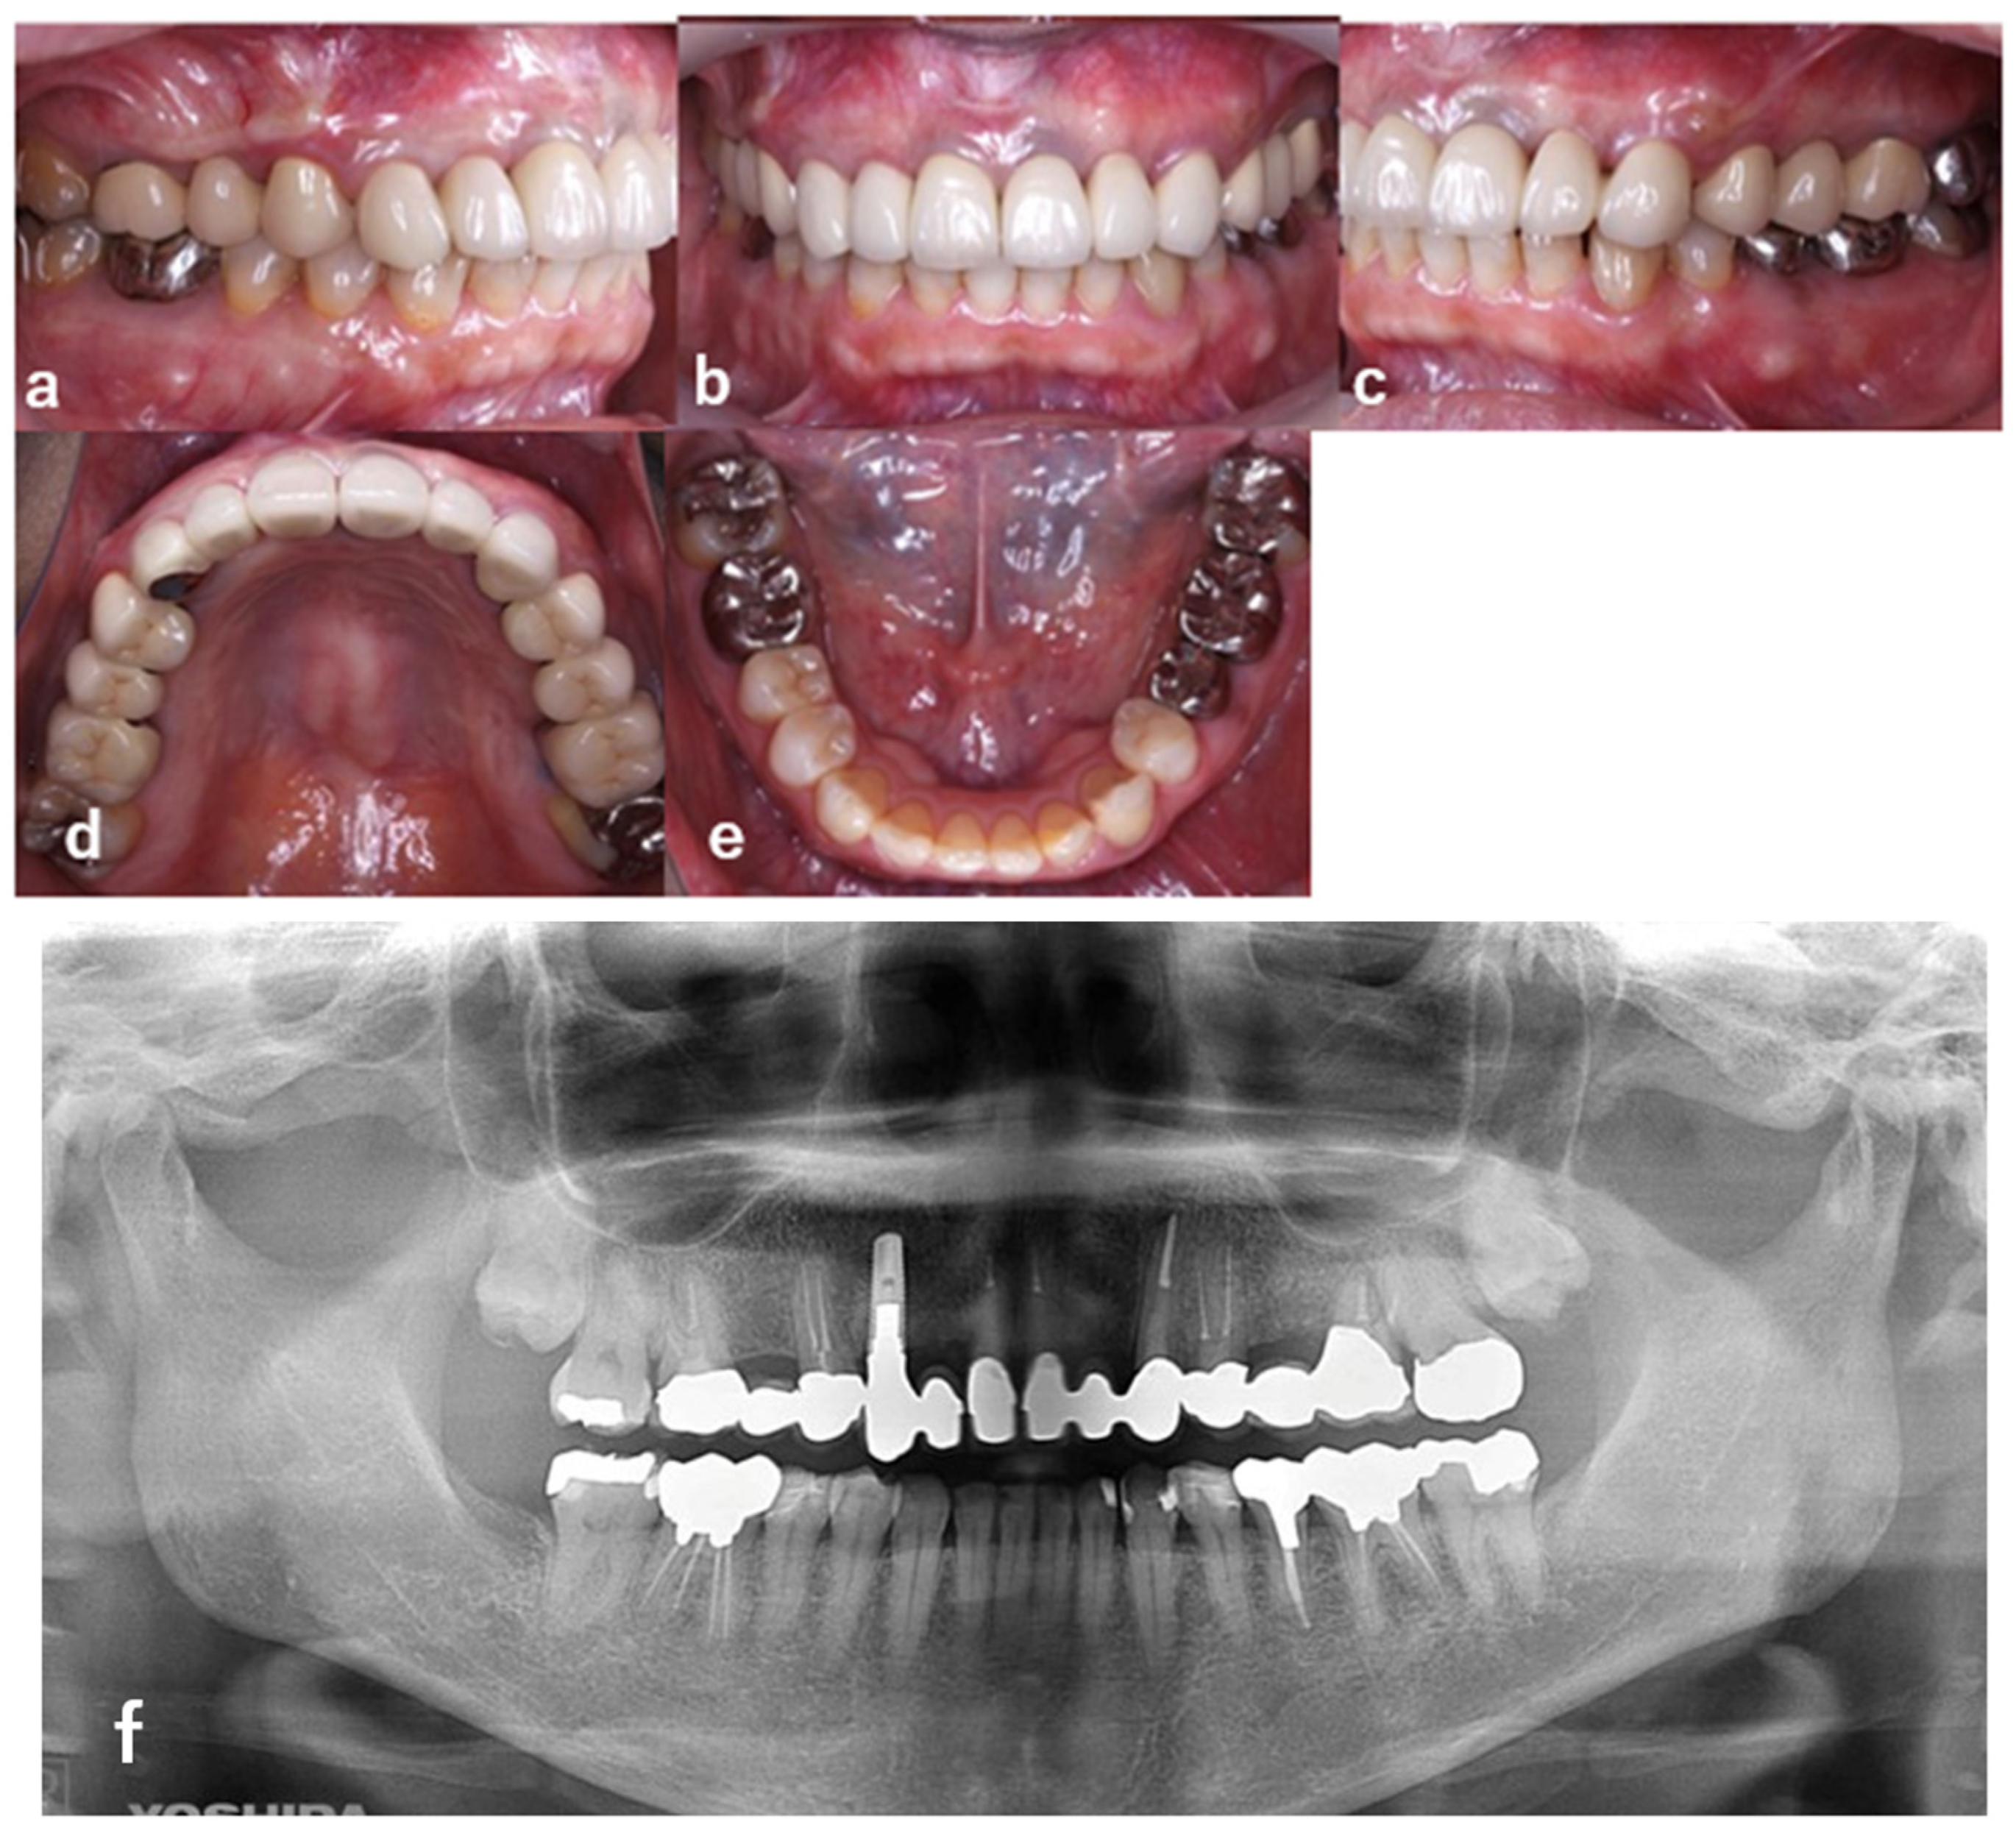

| 1 | Initial visit (August 2015) | Initial assessment & provisionalization | Assessment after traumatic event; long-span provisional restoration to re-establish posterior support and stabilize occlusion (Figure 1 and Figure 2) |

| 8 | +3 months after SGG | Final prosthetic restoration | Delivery of cantilever implant-supported prosthesis (#12–13) (Figure 11 and Figure 12) |

| 9 | Long-term follow-up | Maintenance & evaluation | Regular maintenance; stable peri-implant tissues observed (Figure 13) |